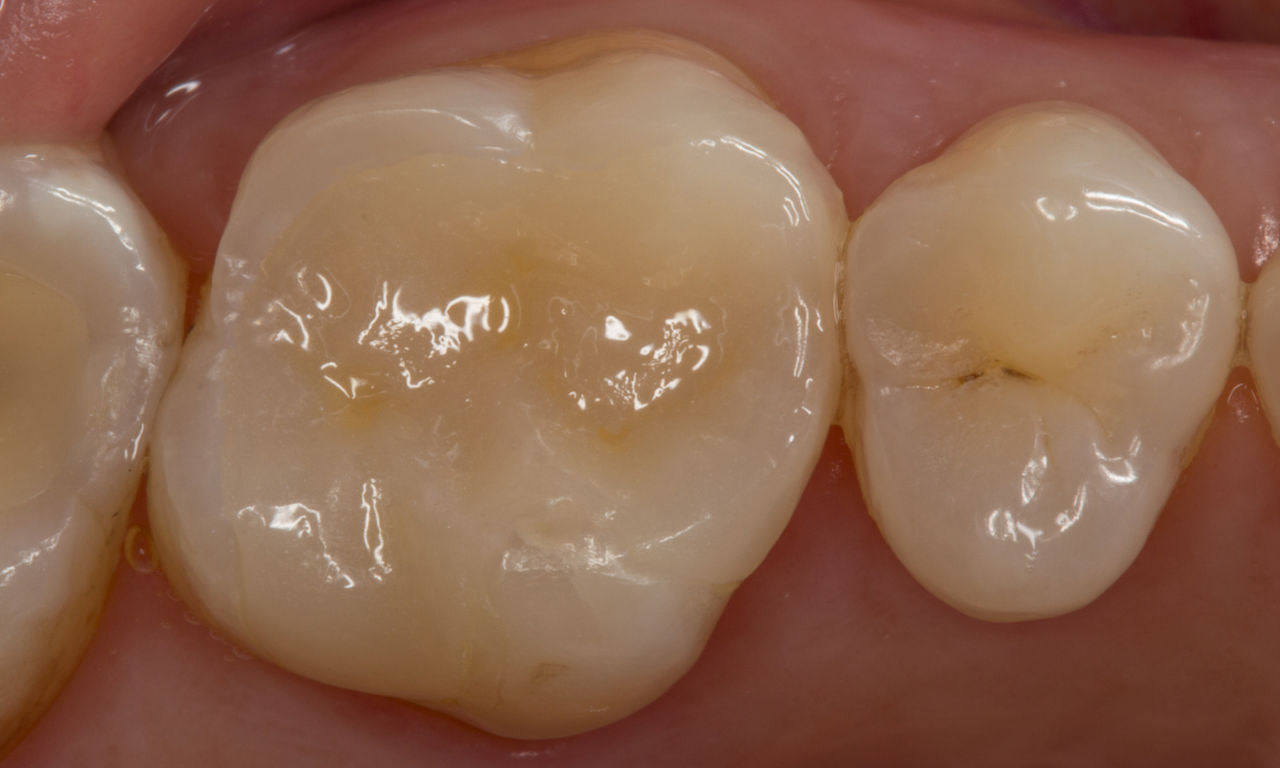

Composite filling, tooth 16, before CEREC treatment

Before

Large insufficiency of the composite filling on tooth 16 with distal marginal ridge cracks, a lingual wall crack and distal recurrent decay.

After

Highly esthetic full-surface glass-ceramic crown.